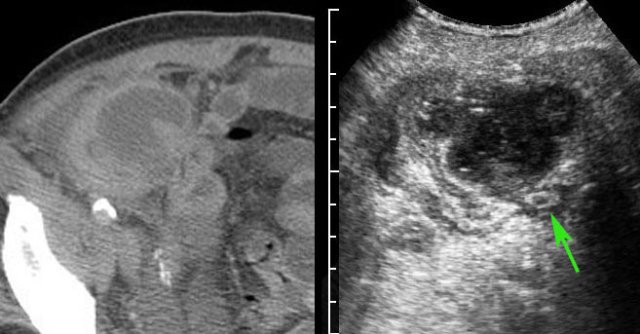

Man of 70 years, with a large abscess in the RLQ.

On CT the appendix could not be identified.

US confirms an inflamed appendix (arrow).

If an appendiceal abscess is demonstrated and there is absent or only mild peritonitis, percutaneous drainage is the treatment of choice.

Dependent of symptoms and US/CT findings, acute laparotomy and wait-and-see are also options.

In the majority of patients with an appendiceal abscess, percutaneous drainage is the treatment of choice.

CT is necessary to confirm the diagnosis, to delineate the extent of the abscess and to determine a safe access route.

Drainage using a combination of US and fluoroscopy has several advantages over CT guided drainage: it is rapid, allows continuous control, any angulation and the use of compression during the procedure.

This patient had a large appendiceal abscess, walled-off by ileum and cecum.

A small window (arrow) allowed US-guided puncture.

Insertion of the drain over a guidewire was done under fluoroscopic control.

In this obese patient, drainage with the US probe using compression, allows the needle to approach the abscess closely.

Note that compression here reduced the distance skin-to-abscess from10 to 3.5 cm.